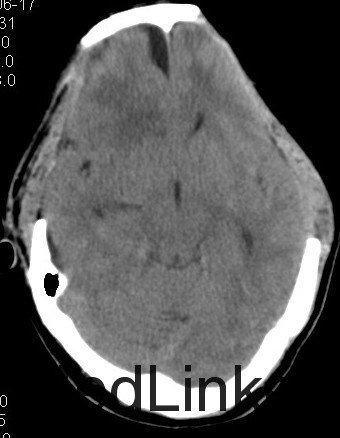

主诉:头部外伤7小时 病史:患者于7小时余前不慎从2米高处坠落,头部着地,并昏迷,左侧外耳道出血,无呕吐,无肢体抽搐,无明显头晕及头痛,无胸闷心悸,呼120入我院急诊诊治,行头颅CT提示有:头部螺旋CT平扫:1、蛛网膜下腔出血;大脑镰硬膜下出血;双侧额叶脑挫伤;脑肿胀。2、左侧枕骨骨折;左侧顶枕部头皮下血肿。3、双侧筛窦炎症。入急诊后患者神志转清,在急诊给予止血、脱水等治疗,4小时后复查头颅CT提示血肿增大及挫裂伤较前明显加重,为进一步治疗,收入我科。患者起病前,精神食欲可,二便可,体重无明显变化。

查体:神志昏睡,间断烦躁,刺激可睁眼,无对答,查体不合作,双侧瞳孔等大等圆,直径3mm,对光反应尚可,枕部可见隐约血肿,约1*1cm,左耳见血性液体流出。深浅感觉查体及腱反射查体不合作,双侧病理征未引出。格拉斯哥评分9分。 4:辅助检查:头部螺旋CT平扫(套:1、蛛网膜下腔出血;大脑镰硬膜下出血;双侧额叶脑挫伤;脑肿胀。2、左侧枕骨骨折;左侧顶枕部头皮下血肿。3、双侧筛窦炎症。颈椎螺旋CT平扫+三维:寰椎与枢椎齿状突之间高密度影,考虑撕脱骨折与钙化灶鉴别,建议复查或MRI进一步检查。

诊断:1、双侧额挫裂伤; 2、大脑镰、右侧额颞硬膜下出血;3、右额颞脑出血; 4、左枕骨骨折; 5、中枢神经系统感染 主要经过:入院后完善术前相关检查,行右侧额颞脑挫裂伤清除+去骨瓣减压+颅内压探头置入术;后行左侧额叶血肿清除+额颞顶去骨瓣减压术,术后予以抗感染、营养神经、改善循环、化痰、护胃、抗癫痫及营养支持治疗。 术后复查CT:双侧额颞顶骨局部缺如;左侧枕骨不连。 双侧额颞顶部皮下软组织稍肿胀。双侧额叶软化灶;右侧额颞部硬膜下及大脑纵裂池积液;右侧额颞部少量积气